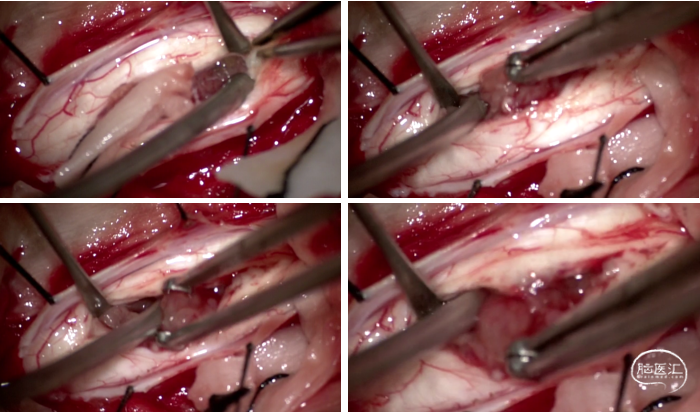

中山大学附属肿瘤医院影像医学中心的刘海彬医师为患者手术提供了高质量的影像学资料,为制定手术方案提供了很大的帮助。完善相关检查,经由神经外科脊髓脊柱亚专业组MDT讨论,骆女士的C1-7、T1髓内肿瘤行C3-6髓内肿瘤显微切除。行肿瘤边界分离,全切肿瘤,避免脊髓损伤,维护脊柱的稳定性,是该手术的目标。张继教授阅片后提出:C3-6髓内肿瘤,脊髓空洞明显,术中需严格肿瘤边界分解,诊断上考虑室管膜瘤可能性大,C3-6后路入路,充分暴露椎板后弓,便可充分显露肿瘤,颈髓后正中沟显露肿瘤,避免术中脊髓牵拉造成对脊髓的挫伤。

图2 术中情况:沿肿瘤两端分离,沿肿瘤边界分离,肿瘤切除后,脊髓中央管通畅,肿瘤全切。